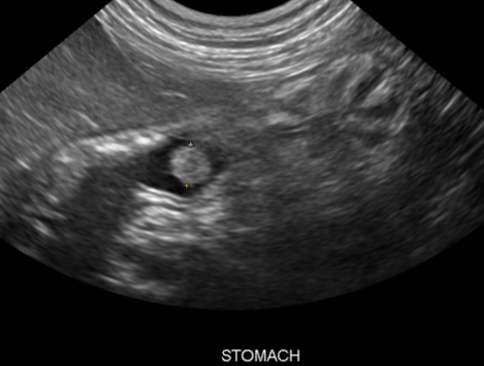

what does ultrasound evaluate in patients with gastric disease?

-evaluates stomach wall layers

-deep ulceration

-masses

-perforation

how is delayed gastric emptying diagnosed?

-abdominal rads to determine if gas or food bloat and evaluate for gastric/pyloric FB

-contrast rad study (evaluate stomach emptying over time, “beak” or “string” sign assoc with pyloric thickening)

-U/S to look for pyloric thickening

-endoscopy or full-thickness surgical biopsies

how is pyloric hypertrophy diagnosed?

abdominal ultrasound and/or radiographic barium contrast studies to document gastric rentention

how are gastric polyps diagnosed?

-ultrasound (homogenous mucosal masses with normal wall layering)

-endoscopy (looks like cauliflower)

-histopathology to confirm